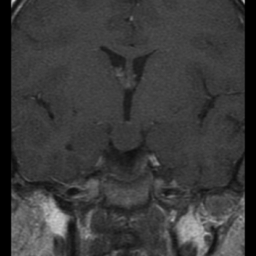

Niña de 7 años. Se solicita RM hipofisaria por pubertad precoz.

T1 + Gadolinio

1. ¿Cuál es tu diagnóstico?

- A. Glioma hipotalámico.

- B. Histiocitosis X.

- C. Hamartoma hipotalámico.

- D. Craneofaringioma.

- E. Germinoma hipotalámico.